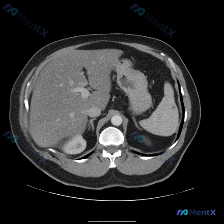

用户预设“存在脾脏病变”,但提供的轴位腹部CT(软组织窗)影像分析结果非常明确:

- 脾脏本身:轮廓清晰,大小正常,实质密度均匀

- 其他腹部脏器:肝脏、胰腺(部分)、右肾均未见明显局灶性病变

- 腹腔整体:血管走行自然,无肿大淋巴结,无游离气体,无积液,各脏器无占位效应

- 直接结论:此特定扫描层面不存在“脾脏病变”的影像学证据